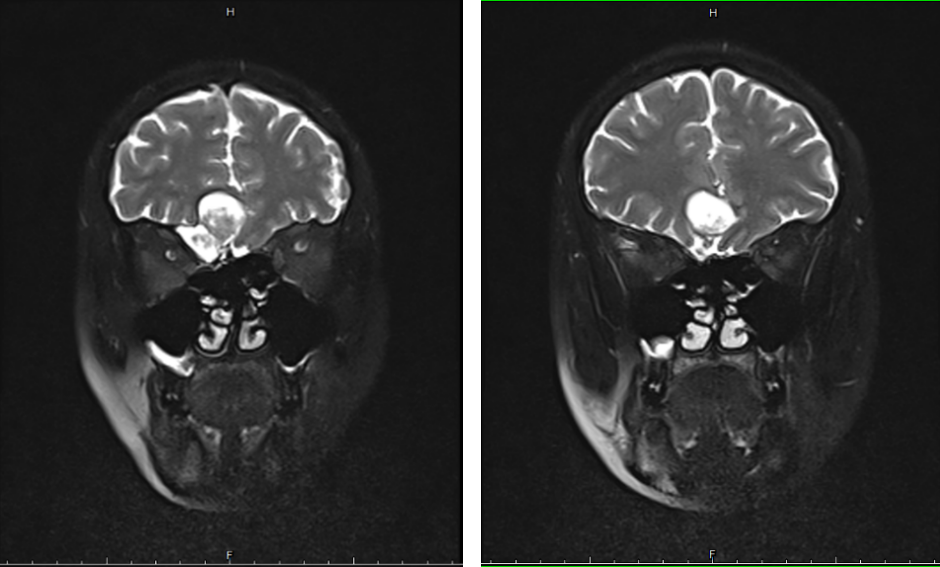

患者因鼻塞、头昏、头痛10余年,并伴有右眼不适感,多次到各级医院就诊,药物治疗效果较差,症状反复发作,逐渐加重。多方打听后来到我院耳鼻咽喉头颈外科就诊,经CT检查后发现右侧筛窦长有一直径约2.5cm大小的肿物,侵犯前颅底以及右侧眼眶,通过科室内部讨论以及全院多学科会诊,考虑为筛窦粘液囊肿侵犯前颅底以及眼眶可能性较大,决定通过鼻内镜下切除筛窦及前颅底肿瘤以改善症状,防止肿瘤继续生长,导致颅内、眶内并发症出现。

相比之传统手术,内镜手术创伤小、时间短,操作精确,患者痛苦轻,术后恢复快。通过手术,可以切除鼻内肿物,达到通畅鼻腔、根治疾病的目的。在耳鼻咽喉头颈外科黄世斌主任带领下,团队采取经鼻内镜下前颅底肿瘤切除术,成功切除了筛窦、前颅底肿瘤,且术中及术后均未出现脑脊液鼻漏、眶内损伤等并发症,手术顺利,术后恢复良好,患者顺利出院。